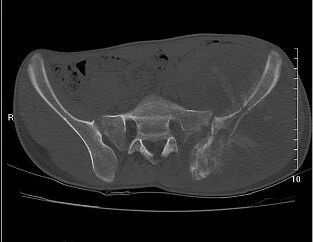

压迫性骨质缺损

压迫性骨质缺损系因骨皮质局部受压,致使骨萎缩以致缺损、消失出现碟形的骨质缺损(图 12、图 13、图 14)。多为邻近骨表面的软组织肿瘤或邻近骨肿瘤压迫或侵蚀骨质所致。一般情况下,骨缺损的边缘都相当锐利且与正常骨质间有明显界限。

图 12.压迫性骨缺损:骨软骨瘤